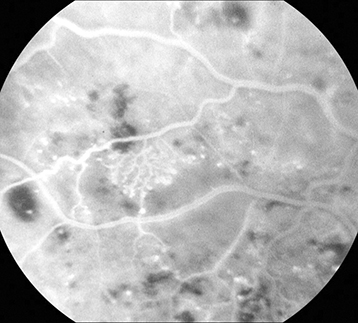

Moderate NPDR: More than mild NPDR, but less than severe NPDR (See Figure 11.12.1). May have CWSs and venous beading.

Severe NPDR: Any of the following in the absence of PDR: Diffuse (traditionally >20) intraretinal hemorrhages in all 4 quadrants, ≥2 quadrants of venous beading, or ≥1 quadrant of prominent intraretinal microvascular abnormalities (See Figure 11.12.2).